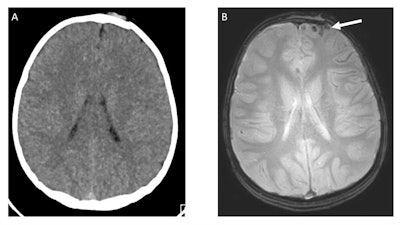

CT scans (Somatom Definition Flash, Siemens Healthineers) included 3D image reconstruction of the skull. Fast MRI was performed on a 3-tesla scanner (Ingenia, Philips Healthcare), with sequences that included axial and sagittal T2-weighed single-shot turbo spin echo (TSE); axial T1-weighed turbo field echo; axial fluid-attenuated inversion recovery (FLAIR) single-shot TSE; axial gradient echo; and axial diffusion-weighted single-shot TSE planar imaging.

As for the modalities' performance, CT identified TBI in 111 patients (50%), with the most common injuries being skull fracture (81 cases, 36%), subdural hematoma (27, 12%), and subarachnoid hemorrhage (24, 11%). Fast MRI identified TBI in 103 of the 111 CT cases and achieved sensitivity of 93% and specificity of 96%. MRI missed six patients with isolated skull fractures and two cases of subarachnoid hemorrhage.

Conversely, fast MRI identified injuries in five patients that CT missed. Those injuries included three subdural hematomas, two parenchymal contusions, and one subarachnoid hemorrhage (one child had both a subdural hematoma and contusion).

The most-effective MRI sequence for detecting TBI was GRE, which found signs of TBI in 94 patients, followed by T2-weighted single-shot TSE, which identified signs of TBI in 88 patients. The least-effective sequences were diffusion-weighted imaging, at 22 patients, and T1-weighted imaging, at 39 patients.